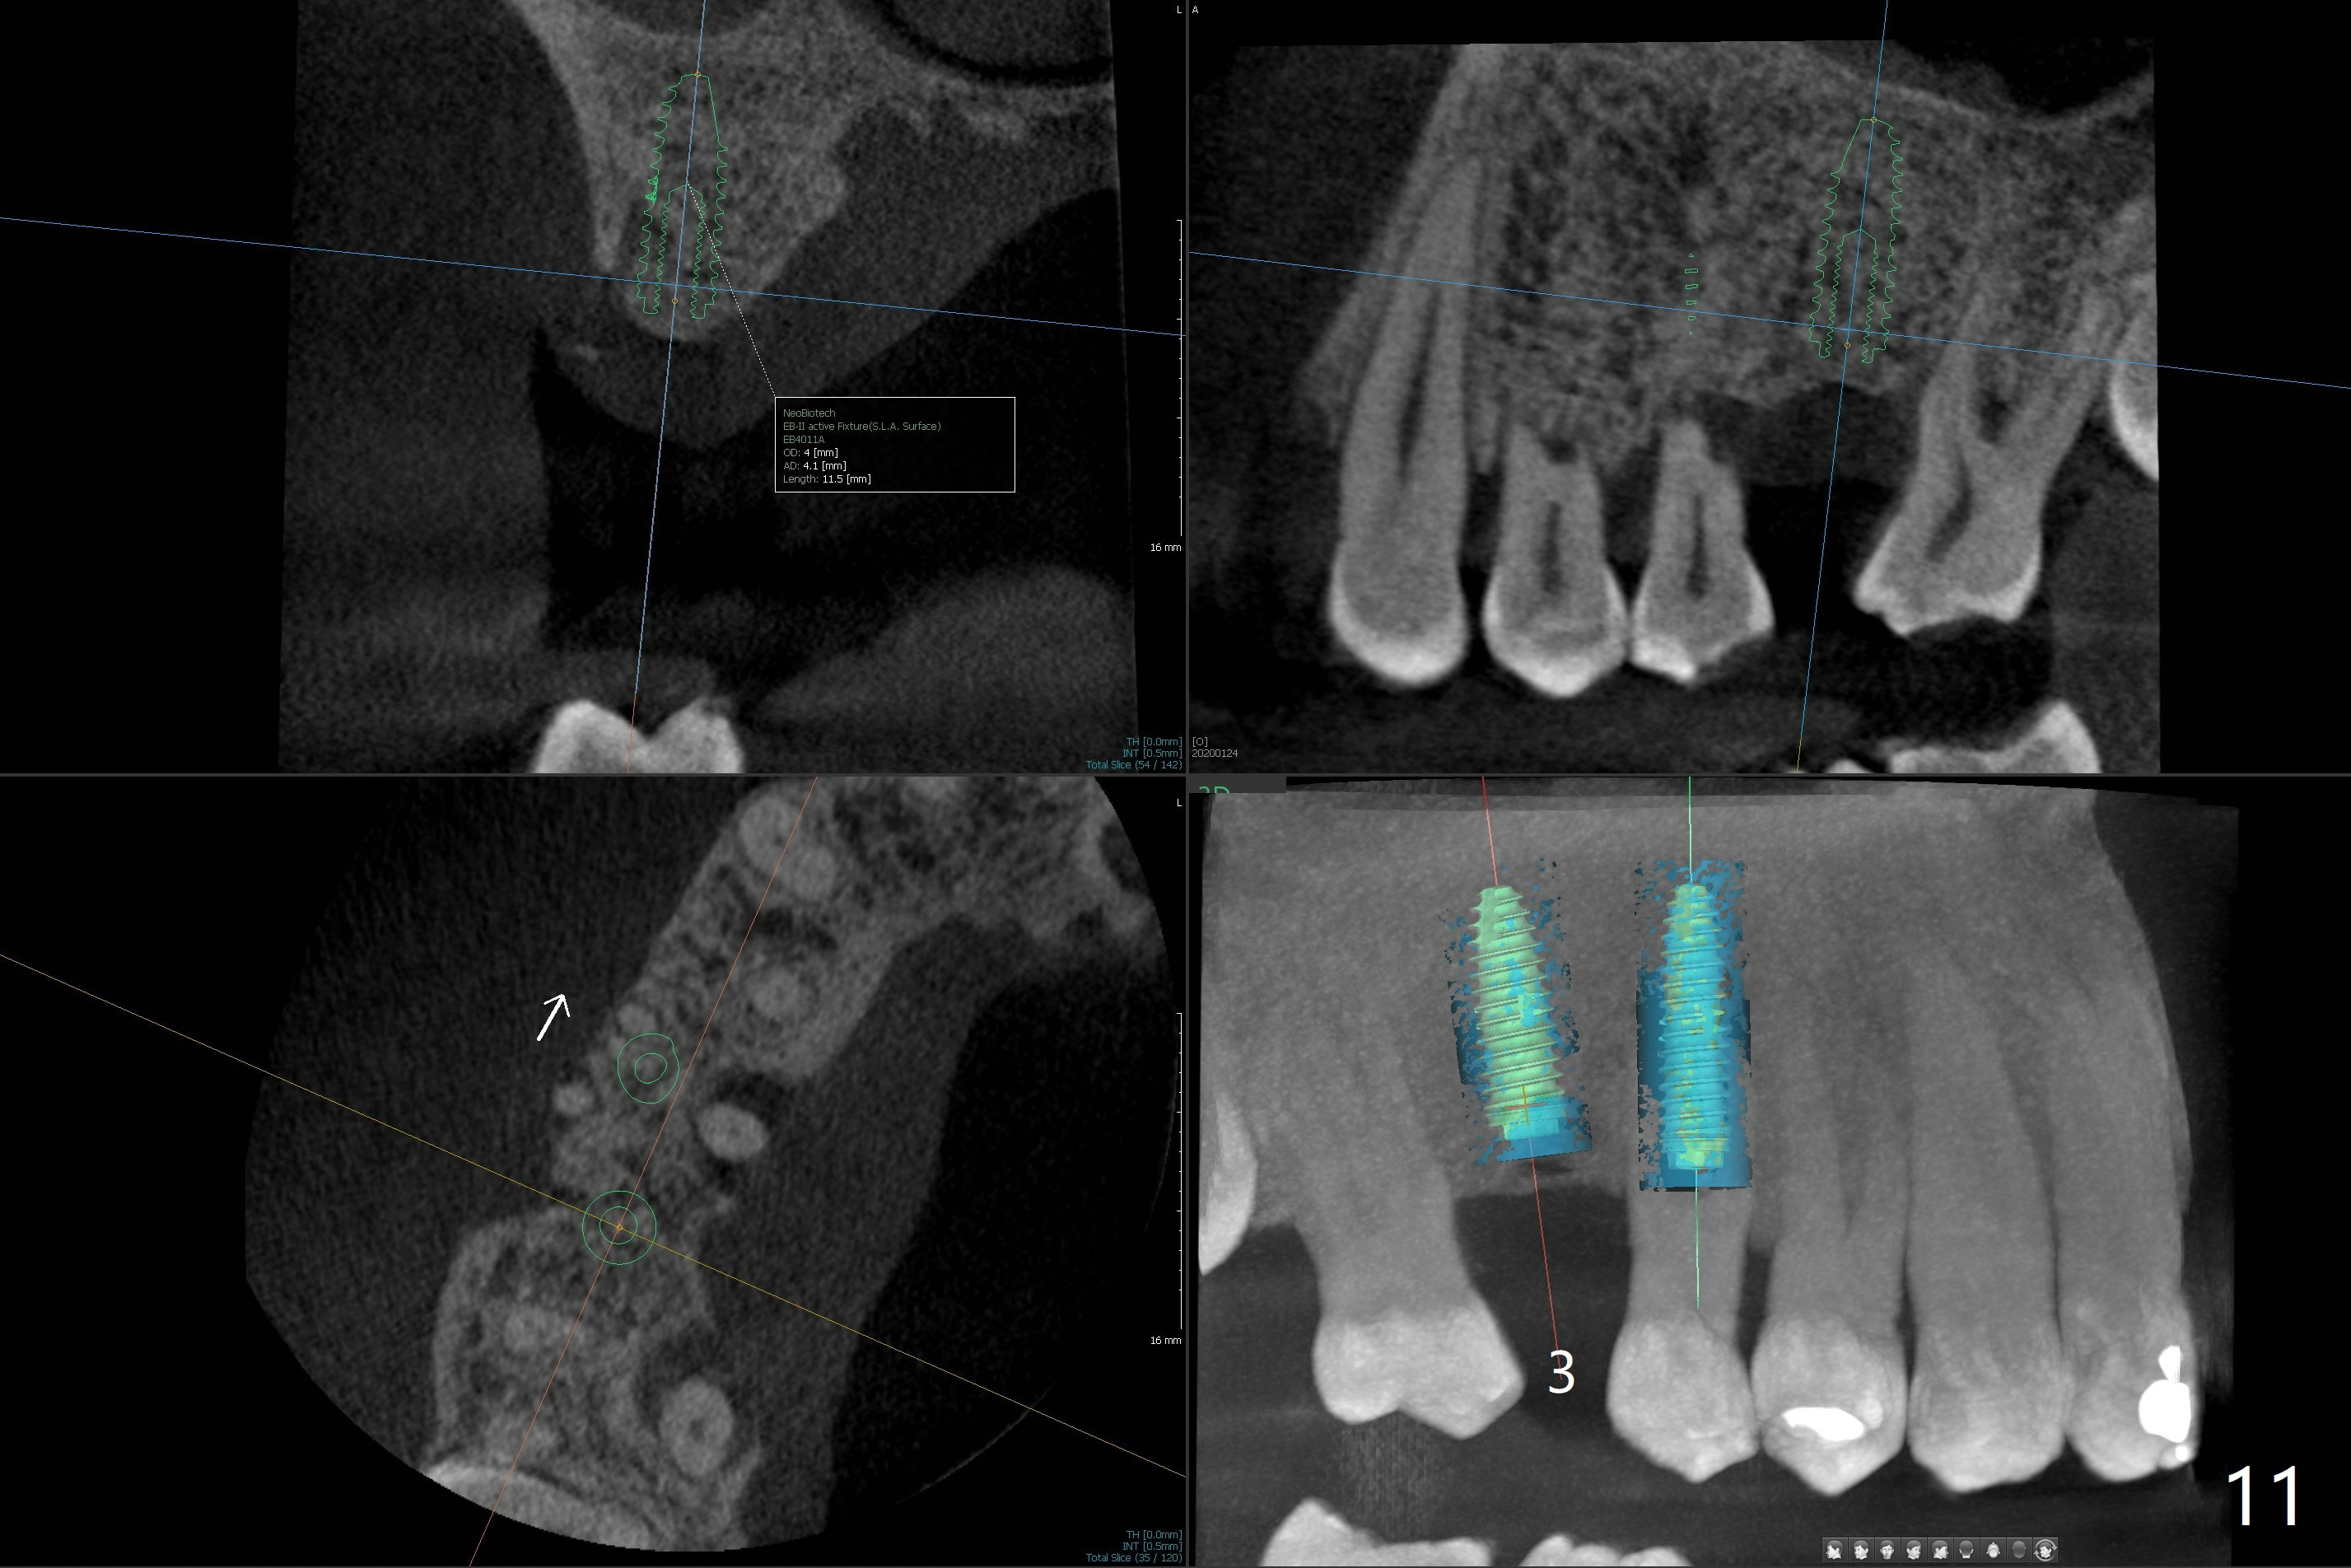

A 52-year-old man (smoker 1 ppd) has toothache in UR. The tooth #4 has severe Class V defect (Fig.1 *), periapical radio-lucency (PARL, arrow-heads) around the buccal roots and mild percu-ssion. PARL is more severe around the palatal root (Fig.2 P). Since it seems difficult to do socket preser-vation, can we do RCT to regrow bone before implant? CT coronal section shows the palatal defect of the palatal root (Fig.3,4), while sagittal one shows J defect of the palatal root, associated with root fracture (Fig.5). In fact the palatal root has transverse fracture at crestal level (Fig.6-8). The tooth #4 will be extracted for immediate implant (Fig.9,10); a 4 mm implant will be placed in the narrow space of #3 at the same time (Fig.11). The patient had symptoms consistent with aortic aneurysm. Since then smoke has been quit.